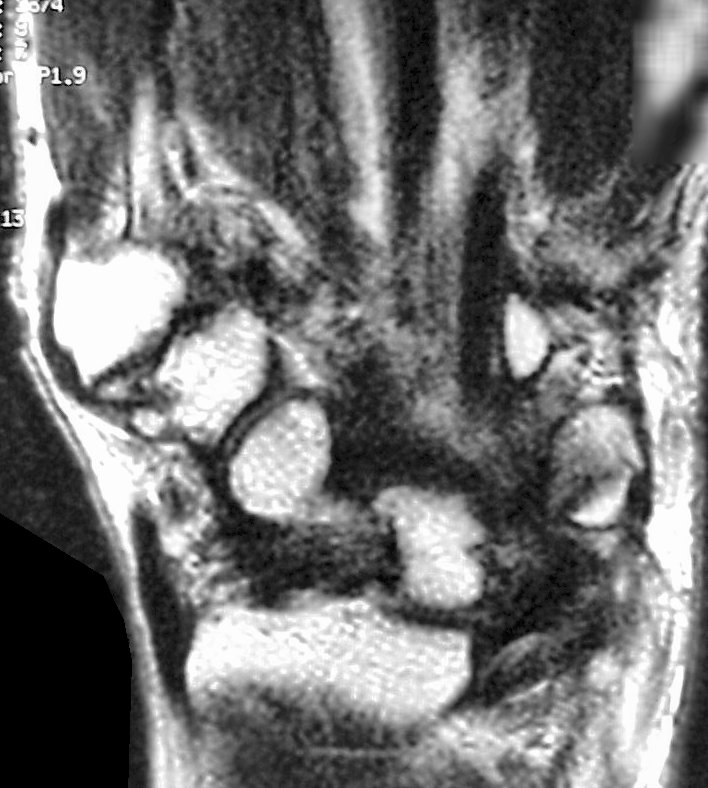

Is that a tendon rupture adjacent to the pisotriquetral joint?

The diagnosis was flexor tendon rupture, site uncertain. He was explored and found to have ruptured both flexors of the small finger within the carpal tunnel: